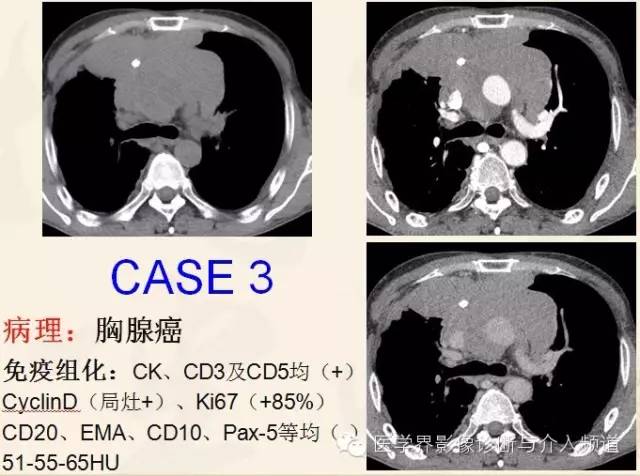

胸腺瘤(Thymoma)

近期WHO依胸腺瘤的上皮细胞形态及其与淋巴细胞比例,将其分为A型、AB型、B型和C型,该分型可作为独立预后因素,并与肿瘤侵袭性、复发等密切相关。

恶性胸腺瘤:肿瘤呈软组织肿块,形态多不规则,可呈分叶状,内部密度不均匀,囊变坏死多见,少数可见钙化,增强扫描多数呈不均匀强化,大血管被挤压、推移或包绕,部分可见肿瘤突入血管内。